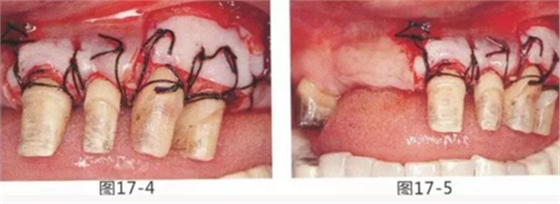

58歲女性,在修復(fù)治療前,為了去除牙周袋和獲得附著齦,頰側(cè)進(jìn)行APF(齦瓣根尖側(cè)轉(zhuǎn)移),FGG(游離齦移植),舌側(cè)進(jìn)行APF(齦瓣根尖側(cè)轉(zhuǎn)移)進(jìn)行對(duì)應(yīng)的病例

圖18-1 右上4,5,6,6,7部位,初期治療結(jié)束時(shí)牙齦的狀態(tài)。

圖18-2 手術(shù)前同部位的口腔X光片。

圖18-4 去除臨時(shí)修復(fù)體后的頰側(cè)面照。在手術(shù)前去除右下5,6,7的金屬樁可以使手術(shù)更為方便。右下5,6部位基本看不到角化牙齦。

圖18-5 同部位的舌側(cè)面照片。角化牙齦較少,將牙槽嵴頂預(yù)測(cè)切開的話很有可能會(huì)沒有任何角化牙齦。